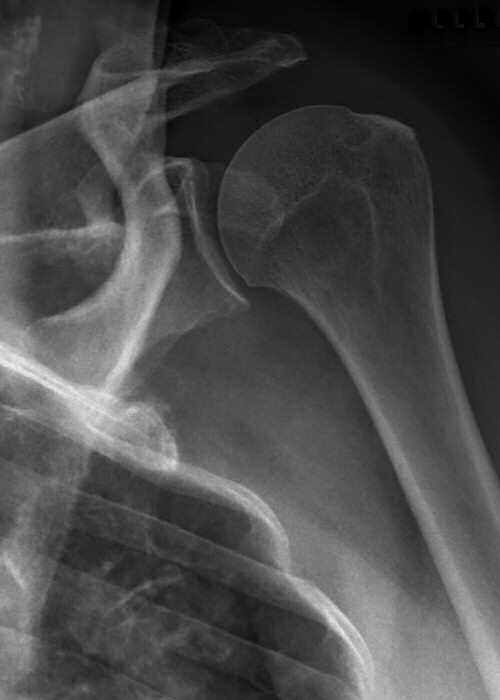

Främre luxation

Efter reponering